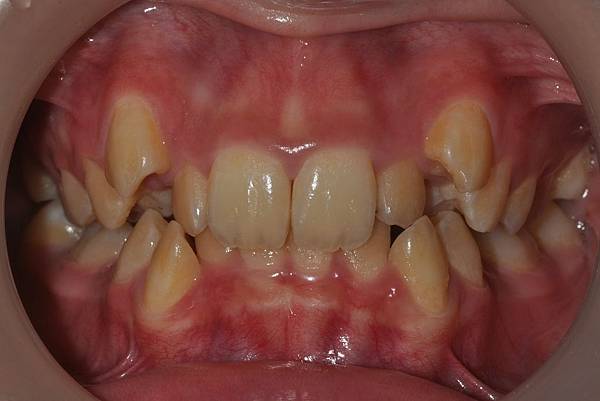

拔牙改善高位虎牙

虎牙妹的女神蛻變之旅~

此案例因為空間不足排列牙齒,

考量到不拔牙將使得牙齒前凸破壞患者原本和諧的側臉。

故上下左右各拔一小臼齒。

治療前/治療後

-以上案例由林昇進醫師提供